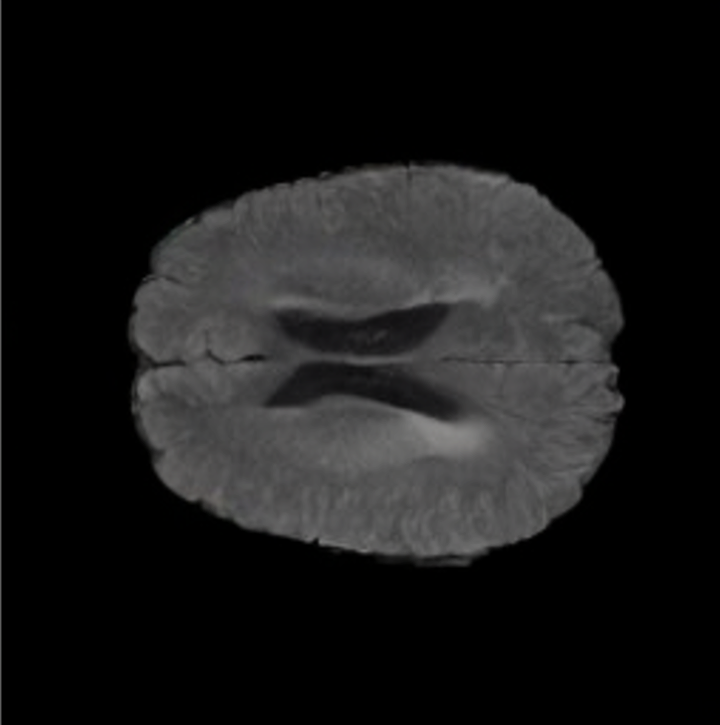

Brain Volumes Preservation. The generated MRIs by our X-Diffusion retain almost the exact same average brain volume vs. of the real MRIs.

Tumour Information Preservation. For the brain tumor segmentation, we use a Swin UNETR model[28, 70], trained with random rotation, and intensity as data augmentation. On the test set with human ground-truth annotations (), the brain volumes generated from single slice input preserve the volume of the different tumour components (paired t-test, for all 3 classes). In Figure 4, we highlight the tumor profiles of the generated MRIs compared to the ground truth tumour profile. The real MRI Dice score in the test set is 85.15 while the generated MRIs from a single slice have a dice score of 83.09. This shows how the generated MRIs indeed preserve the tumor information and can act as an affordable and informative pseudo-MRI, before conducting an actual costly MRI examination in hospitals. More detailed results are provided in supplementary material.

Leveraging Context. Since we train on a predominantly cancerous brain dataset, one question that might arise is whether X-Diffusion generated MRIs preserve tumour information when the given inputs do not intersect with any tumour. We perform experiments varying the input slice index used to generate the 3D brain MRIs and measure the performance for input slices with no intersection with the tumour (not a single pixel with tumor label in the input slice). We also measure performance when only input slices are selected from tumor range. The Dice Scores of the random slices, no-tumour, and only-tumour are 83.09, 79.23, and 83.68 respectively. As can be seen here, the brain volumes generated from input slices with no tumour still preserve tumour information in reconstructed brain volumes despite a small drop in performance. This indicates that X-Diffusion is leveraging the context to preserve key information, such as tumor locations. This observation is consistent with how tumor segmentation models with global context [13] perform better than local-based U-Nets. More details are provided in supplementary material.